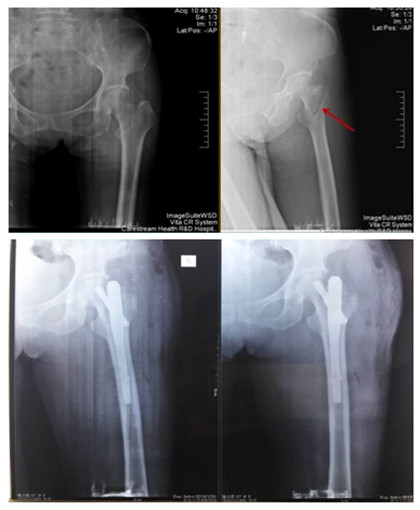

我院首例股骨粗隆间骨折PFNA技术